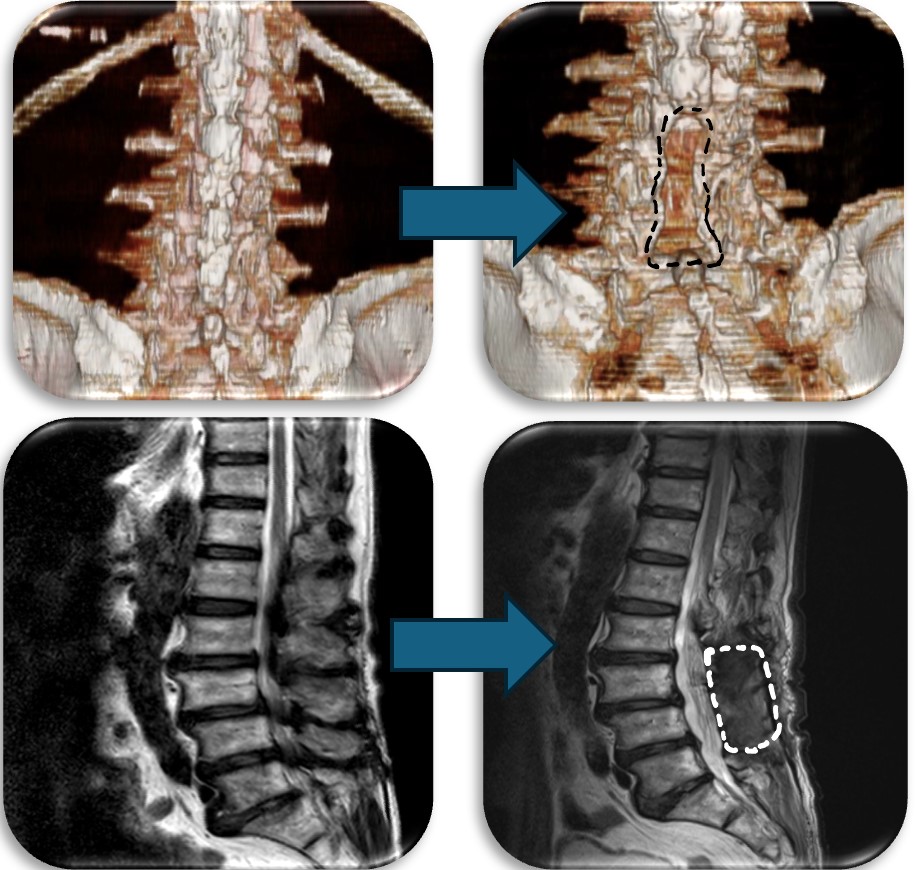

(代表例②)

腰部の脊柱管狭窄症に対して、腰の後ろから手術する椎弓切除術を行なった症例です。脊柱管と呼ばれる脊髄が通るトンネルの屋根部分にあたる椎弓を切除(点線部分)することによって狭かった脊柱管を広げます。

(代表例③)

腰部の脊柱管狭窄症に対して、腰の側方から徐圧し、後方から固定術(OLIF)した症例です。椎間板が摩耗していたり、不安定性がある症例、後方からの手術歴があり再手術症例に適した手術方法です。狭小化した椎間板にスペーサーを挿入(白線)する事により、脊柱管の高さを正常な状態に戻し3次元的に狭窄を改善させます。